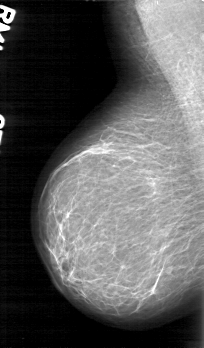

D_4045_1.RIGHT_MLO

RIGHT_CC LINES 5251 PIXELS_PER_LINE 3121 BITS_PER_PIXEL 12 RESOLUTION 43.5 NON_OVERLAY

RIGHT_MLO LINES 5206 PIXELS_PER_LINE 3046 BITS_PER_PIXEL 12 RESOLUTION 43.5 NON_OVERLAY